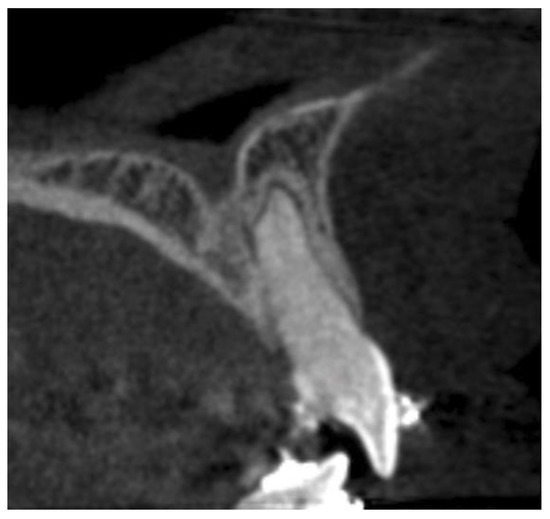

- Horizontal plane separately for each level—L1, L2, and L3:

- Incisive canal width—|Cl-Cl|.

- Antero-posterior IC—|Ca-Cp|.

- Distance between the most mesial point of the root and the tangent passing through the most anterior point of the incisive canal—|Rm-Cat|.

- Distance from Cl to the posterior edge of the incisor root—|Cl-Rpt|.

- Distance between roots |Rm-Rm|.